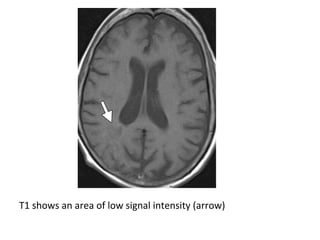

T1 shows an area of low signal intensity (arrow)

T2 shows an area of high signal intensity (arrow)